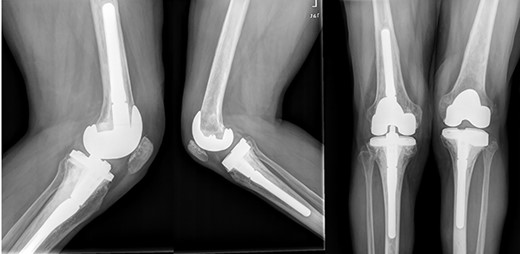

In the early postoperative period, no complications were detected, with pain decrease. After 4 years, the patient’s active ROM was 0–110° bilaterally, with no signs of radiological loosening (Fig. 9) and no pain, leading an unrestricted walking daily life without aids.

Both knees standing radiographs at 4-year follow-up with no signs of radiological loosening.